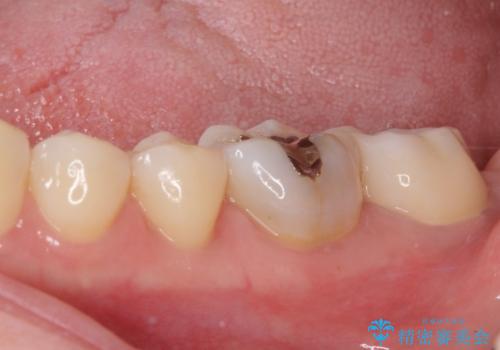

奥歯が痛い 保険治療後に症状が発現した歯のむし歯治療

- 近医にてむし歯治療を行った後に痛みが出たとのことで来院された患者様です。

左下奥歯は術後から咬合時の痛みが発現し、来院時には脈を打つような痛みが認められました。

診察の結果、神経を取り除く必要があると判断されたため根管治療を行いました。

その後、左上の奥歯にも咬合時の痛みが認められ、レントゲン写真より歯内の神経が失活していることが分かりました。

2歯ともに根管治療を行い、その後はオールセラミッククラウンにて補綴治療を行うこととしました。